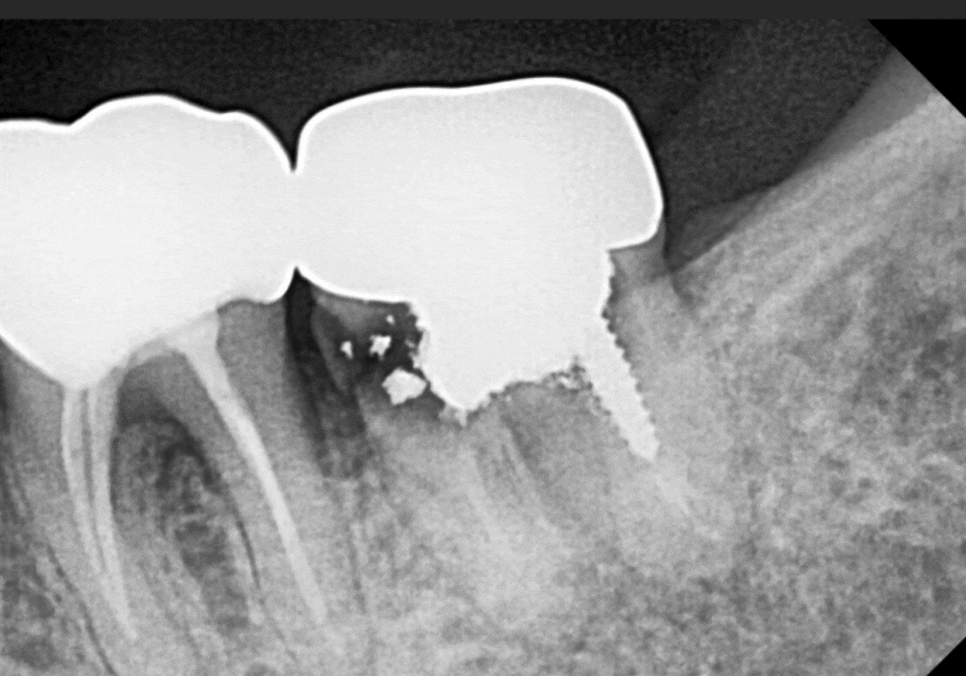

더 자세히 살펴보기 위해 CT를 확인해 보니,

뿌리 끝 염증이 까맣게 퍼져 있었는데요.

특히 치아 뿌리 바로 아래를 지나가는

'하치조 신경' 근처까지 뼈가 녹아 있었습니다.

이 환자분처럼 신경과 가까운 곳의

뼈가 다 녹아버린 상태에서

무리하게 임플란트를 심으면 어떻게 될까요?

신경을 피하려다 보니

임플란트가 뼈에 박히지 못하고

거의 허공에 떠 있는 상태가 되어버립니다.

당연히 튼튼하게 고정될 수가 없겠죠~?

그래서 뼈이식이

필요한 겁니다.